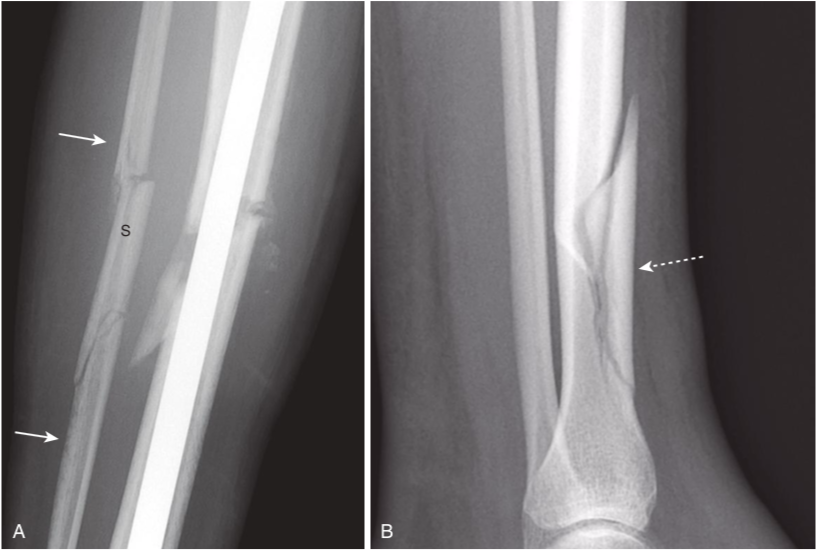

Segmental fracture and butterfly fractures.

These are two comminuted fractures. A,There is a segmental fracture in which a portion of the shaft exists as an isolated fragment. Notice how the fibula has a center segment (S) and two additional fragments, one on either side (white arrows). B,A butterfly fragment is a comminuted fracture in which the central fragment has a triangular shape (dotted white arrow).

Transverse, diagonal, and spiral fracture lines.

A,In a transverse fracture (white arrow),the fracture line is perpendicular to the long axis of the bone. B,Diagonal or oblique fractures (black arrow)are diagonal in orientation relative to the normal axis of the bone. C,Spiral fractures (white arrows)are usually caused by twisting or torque injuries.